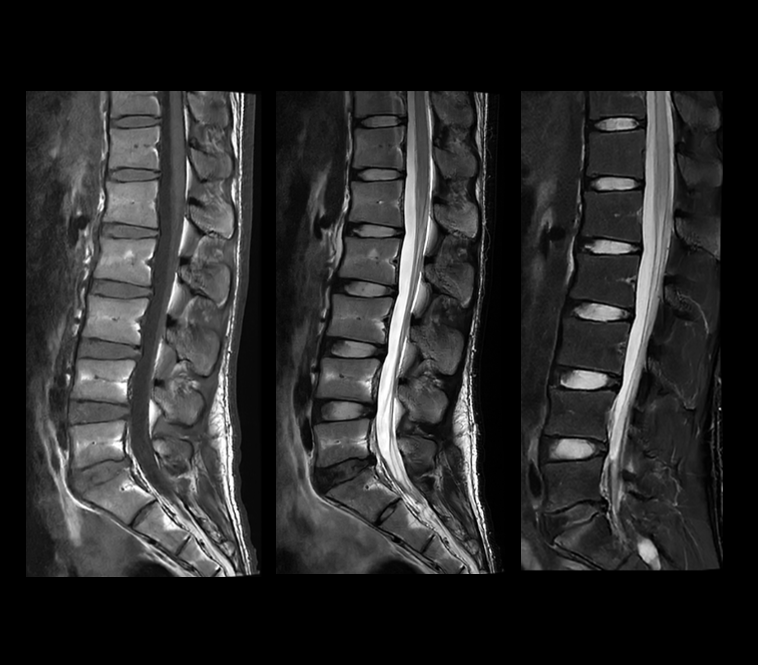

搭载uAIFI Technology技术平台,凝聚多项全球首创核心技术,全链条革新磁共振硬件、软件设计,实现系统性能、扫描智能化、成像速度与信噪比的大幅提升,同时赋予患者更舒适的检查体验,开启磁共振“类脑”时代。

在uMR 880上,我们将全身型磁共振的梯度性能推向了新的高度。更高的梯度梯度性能在弥散扫描时可以帮助用户获得更短的TE时间以提升信噪比同时得到更准确的弥散模型。